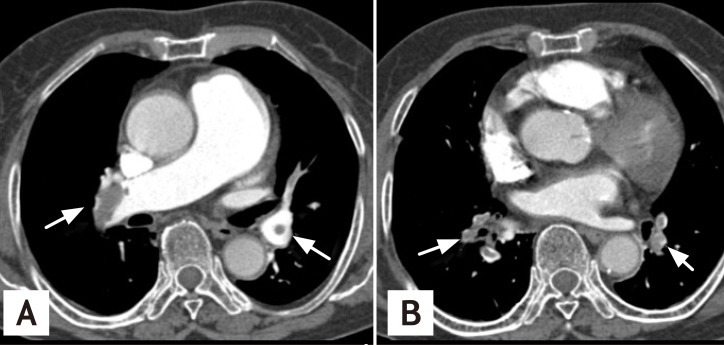

Figure 1

(A, B) Chest computed tomography reveals extensive intraluminal filling defects in the right main pulmonary artery. The lobar, interlobar, and segmental branches are consistent with acute pulmonary embolism (arrows).